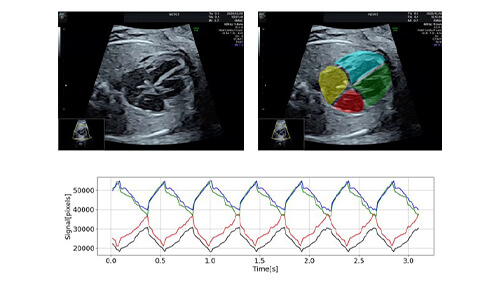

Examples of DX initiativesAI-Based Diagnostic Support System for Fetal Arrhythmia Using Ultrasound Videos

- ・We have developed an AI-based system that supports diagnostic processes using only ultrasound videos.

- ・A prototype system designed to automatically identify arrhythmias—such as tachycardia, bradycardia, and extrasystoles—has been completed to support diagnosis.